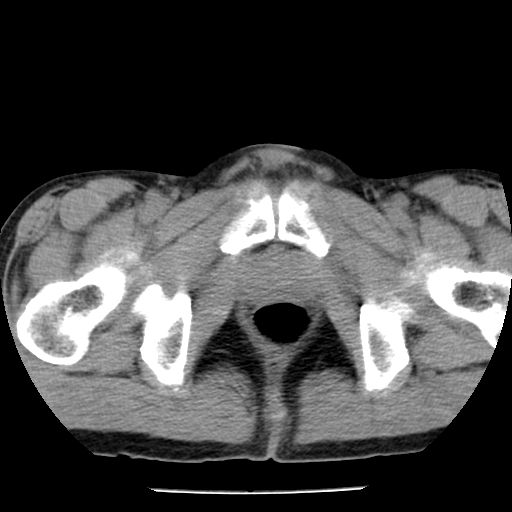

男,59岁,“结核性胸膜炎”30余年,胸部经常疼痛,多次x检查提示“肺部”炎症。腹部疼痛5日,b超提示:“肝内短管结石,余显示不清,建议进一步检查。”

两肺结核并右侧胸腔积液;脾脏、腹腔及腹膜后淋巴结结核[陈旧性];肝内胆管结石

胸部腹部都是结核(双肺。纵隔淋巴结,肝脏,脾脏,肠系膜)